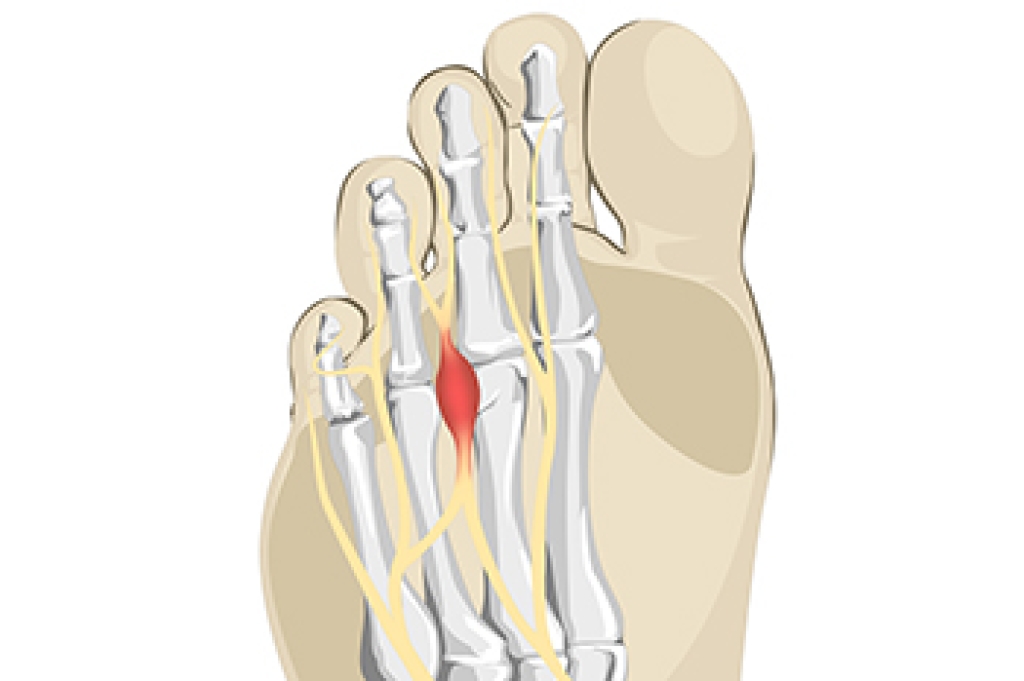

Morton’s neuroma is a foot condition that can develop in women who frequently wear high heels. This condition can result from having inadequate room for the toes to move freely in and can cause the nerve between the third and fourth toes to become compressed. Irritation and inflammation may accompany this, which can cause severe pain and discomfort. Patients who have Morton’s neuroma often say the sensation they feel is similar to having a pebble or marble in the shoe, in addition to numbness and tingling. Mild relief may also be found when soft insoles are worn, the feet are elevated, and shoes that are worn have a wide toe area. Existing medical conditions may contribute to Morton’s neuroma. These can include flat feet, bunions, and hammertoes. If you feel you may have this foot condition, it is advised that you speak to a podiatrist who can properly treat this ailment.

Morton's neuroma is a painful foot condition that commonly affects the areas between the second and third or third and fourth toe, although other areas of the foot are also susceptible. Morton’s neuroma is caused by an inflamed nerve in the foot that is being squeezed and aggravated by surrounding bones.